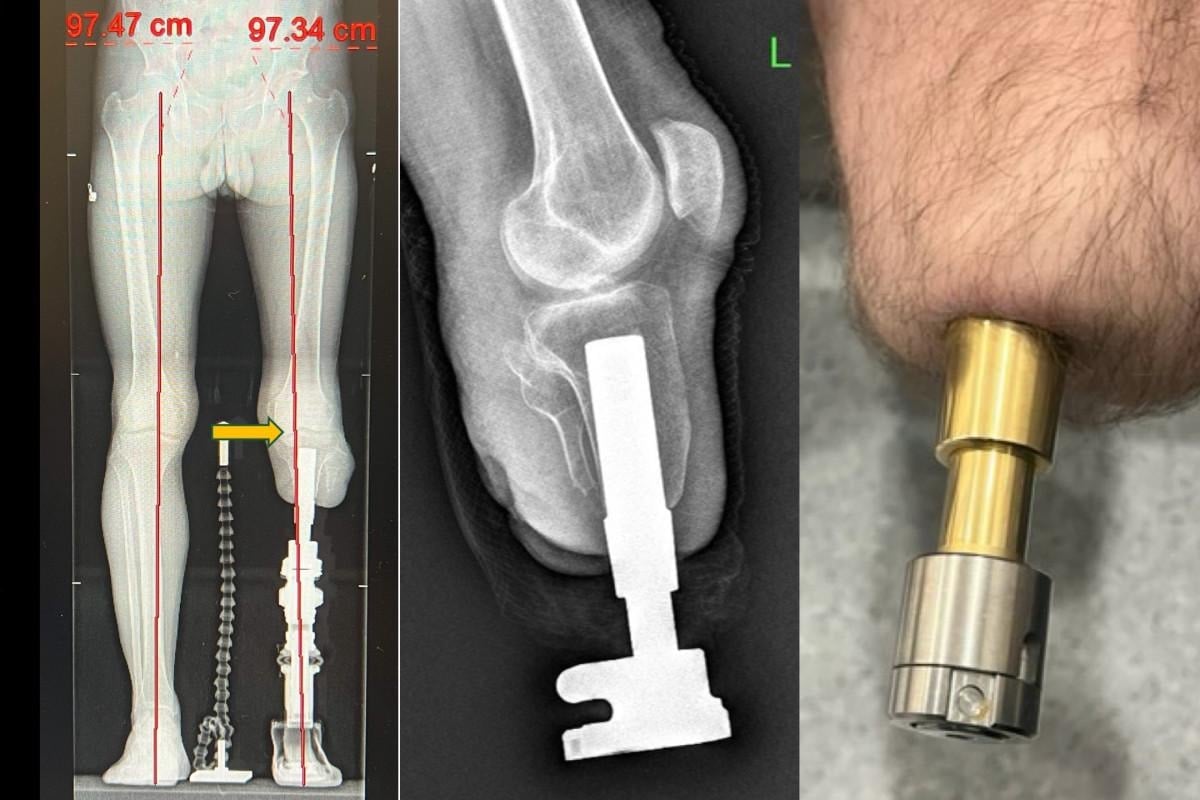

Kemiğe yerleştirilen implantlarla daha doğal ve konforlu bir yürüyüş sunan bu yöntem Türkiye’de de uygulanıyor.

Bu yöntemde, kemiğe yerleştirilen implant sayesinde yük doğrudan kemiğe aktarıldığından, çok daha doğal ve konforlu bir yürüyüş mümkün oluyor.

Osseointegrasyon protezlerinin yapıldığı uzuvlar hakkında da bilgi veren Prof. Dr. Kara, yöntemin uyluk, kaval kemiği, dizüstü ve dizaltı gibi bölgelerin yanı sıra üst kol amputasyonlarında da başarıyla uygulandığını aktardı.